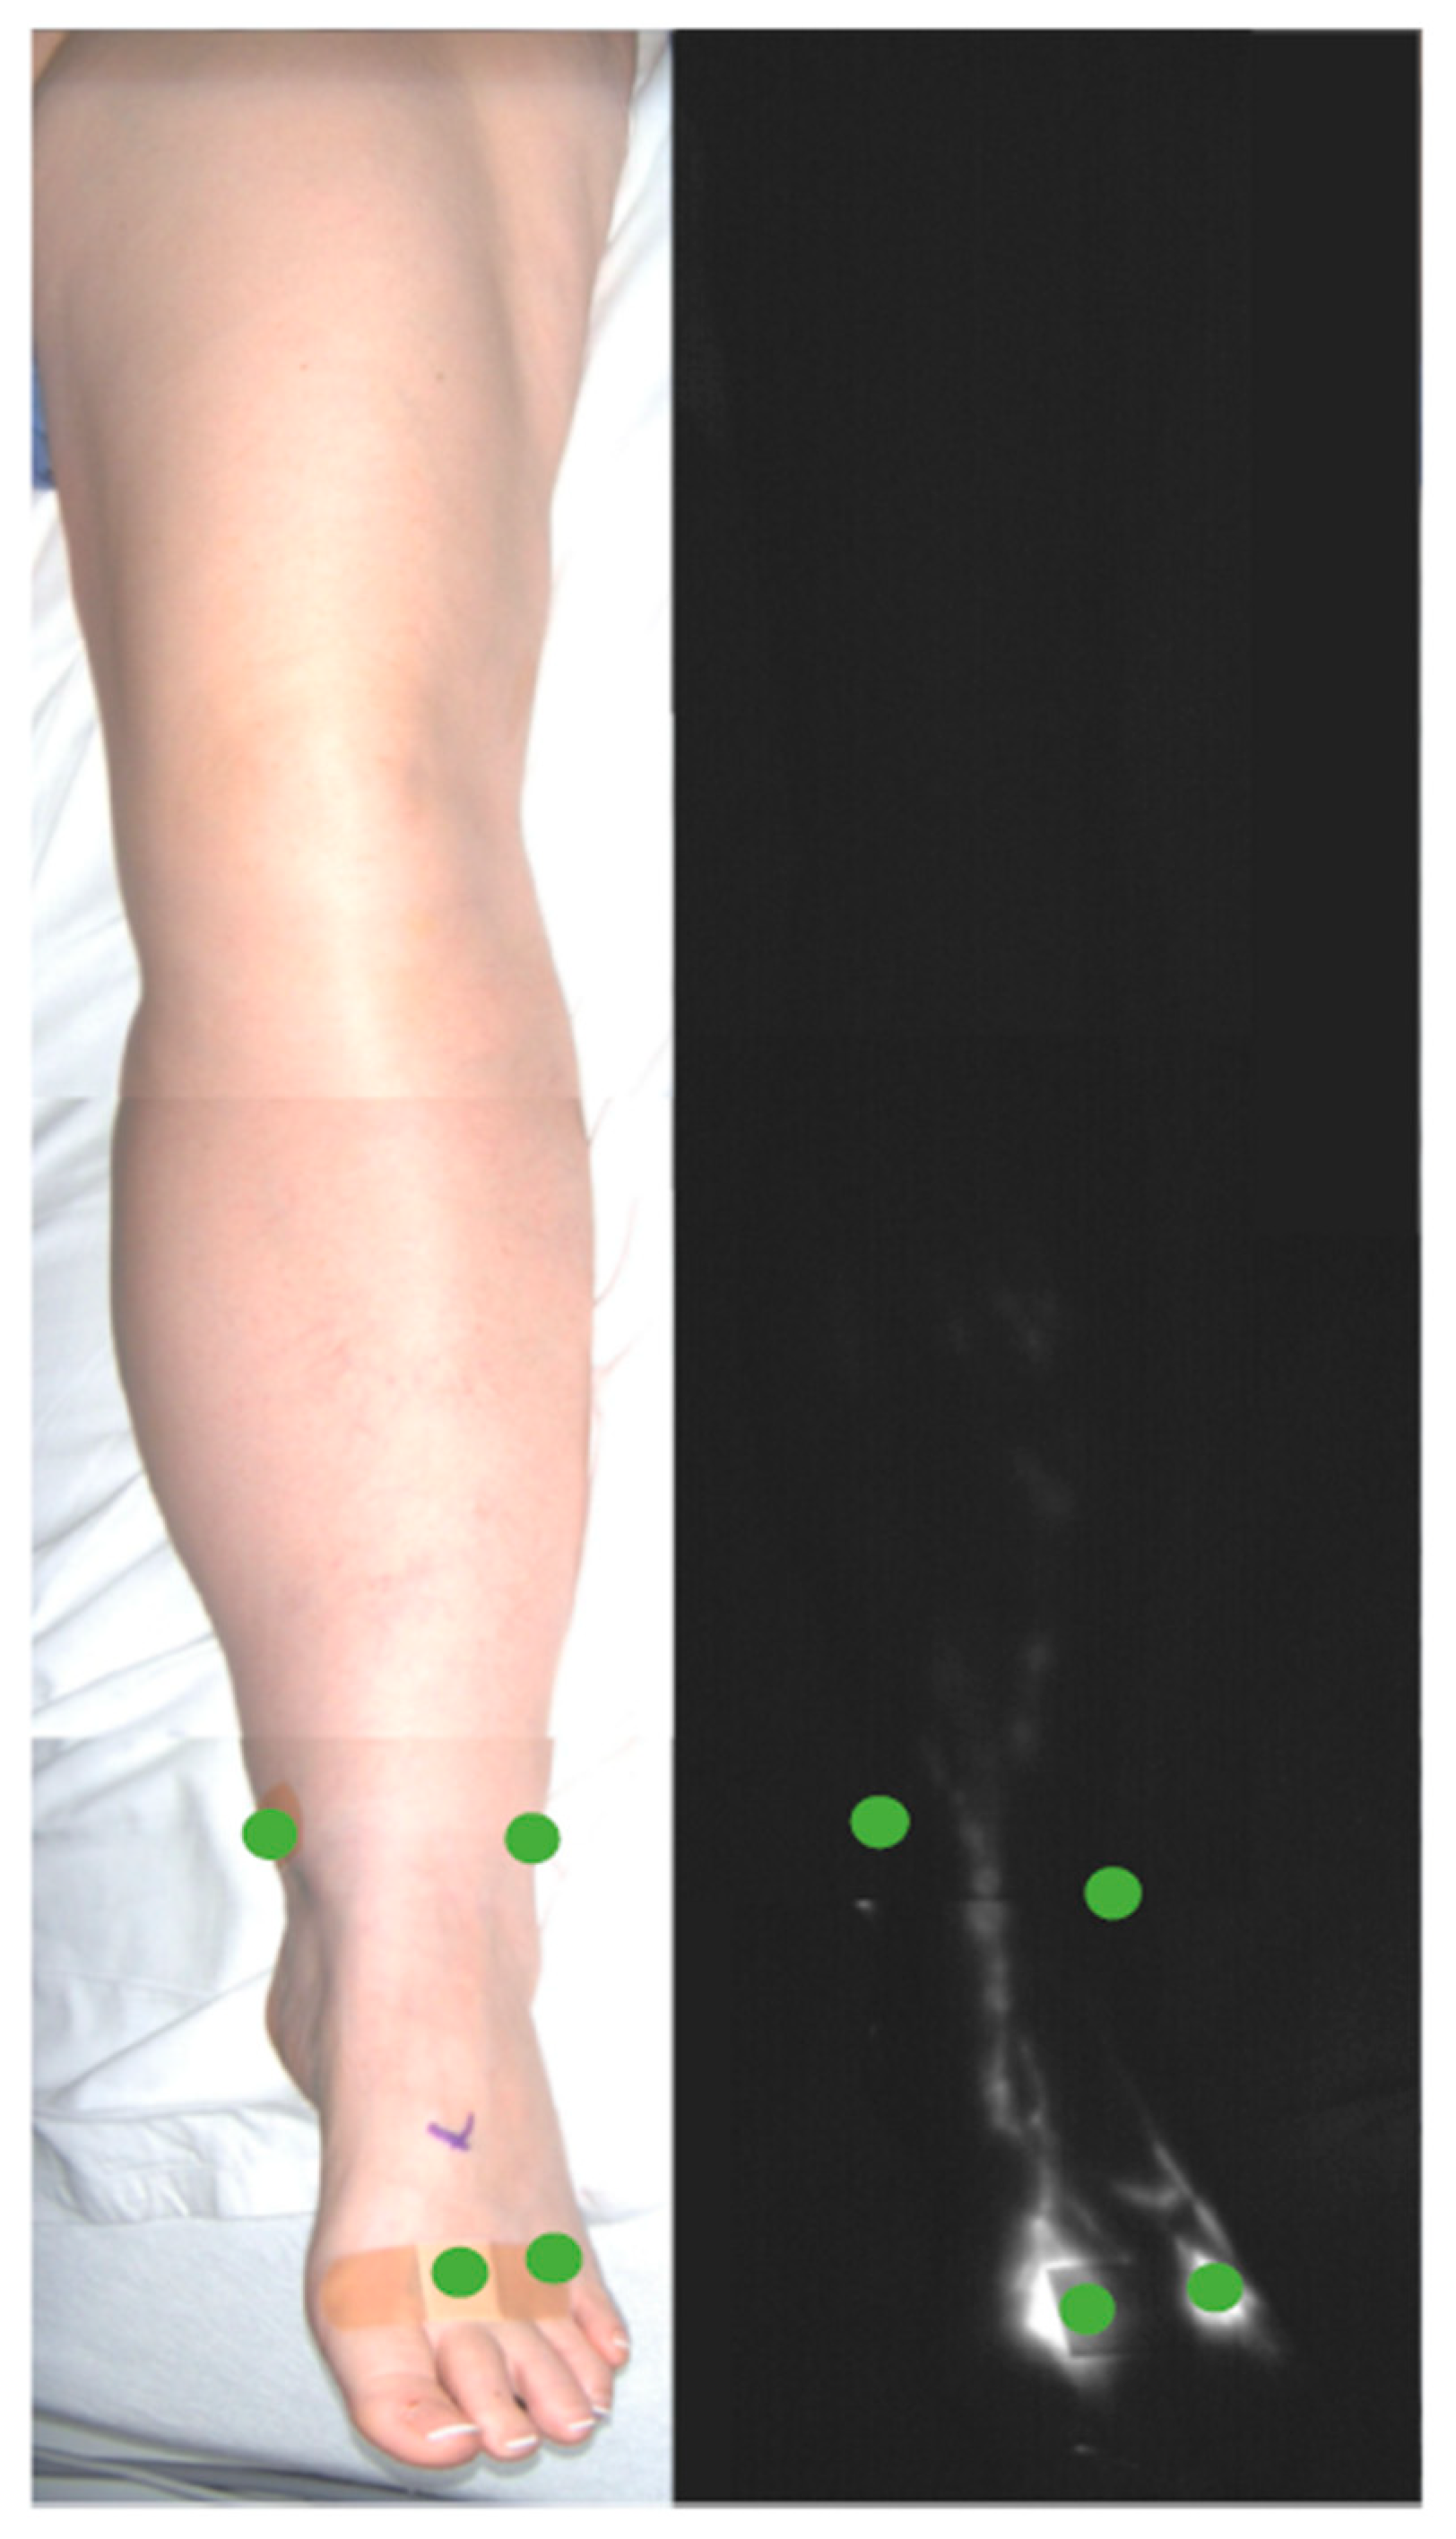

ICG Lymphography